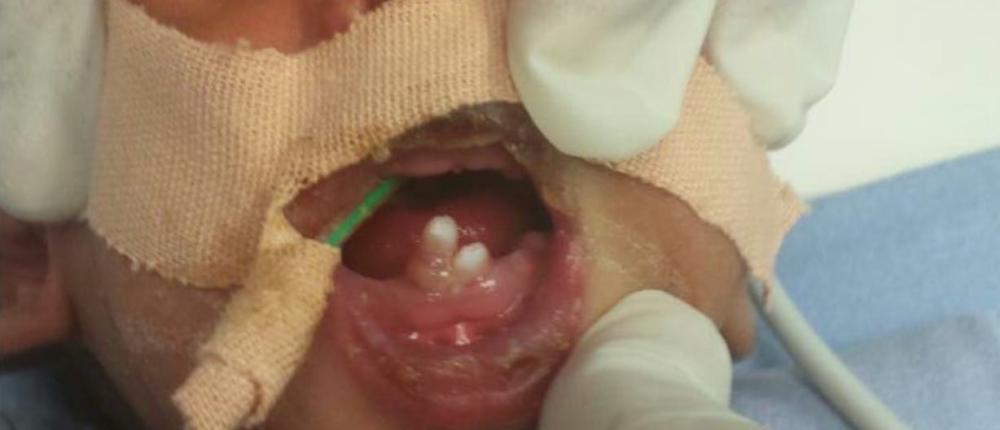

أجرى فريق قسم جراحة الفم والأسنان بمركز طب الأسنان التخصصي بالقريات، عملية جراحية لمولود يبلغ من العمر 7 أيام.

وأوضحت صحة القريات أنه تسبب وجود أسنان في الفك السفلي في هذه المرحلة العمرية المبكرة، قد تتسبب في إعاقة عملية الرضاعة الطبيعية للطفل، إضافة إلى المخاطر المتمثلة في احتمالية بلعها، مما قد يسبب مشاكل تنفسية للرضيع.

يذكر أن ظهور مثل هذه الأسنان أمر نادر الحدوث، ويتطلب سرعة التشخيص والتدخل من قبل المختصين.

عملية نادرة لرضيع.. ولد وفي فمه أسنان!